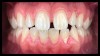

(5. and 6.) Side-by-side comparison of a contemporary smartphone camera image and a DSLR camera system image.

For most dental clinicians and technicians, the acquisition of professional-level photographs with a DSLR camera requires a steep economic investment and possesses a shallow learning curve. The time commitment and nebulous return on investment are certainly potent deterrents to the incorporation of these systems into daily practice. While remaining cognizant of the need for photographic documentation, the dental field has witnessed an increase at the low end of the dental photography continuum through the use of the ubiquitous smartphone as a proxy for the larger and more expensive DSLR camera setups. Most smartphones will allow the user to customize and control the elements of the exposure triangle via the internal camera settings or by means of a third-party application (Figure 4); however, the diminutive nature of the lenses, apertures, and sensors of these devices makes the necessary attainment of light problematic. When this is coupled with low-capacity native light output on the subject being photographed, the resulting images are often distorted, low-resolution, and possess inconsistent reproduction of color and detail, which renders them unacceptable for documenting patient treatment and collaborating with the laboratory (Figure 5 and Figure 6).